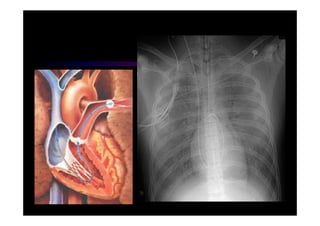

• MONITORIZAÇÃO

•   Rx de tórax AP simples

Choque • MONITORIZAÇÃO • Oximetria • Gasometria Arterial • Bioquímicos: U, C, Na, K • Rx de tórax AP simples • HEMODINÂMICA